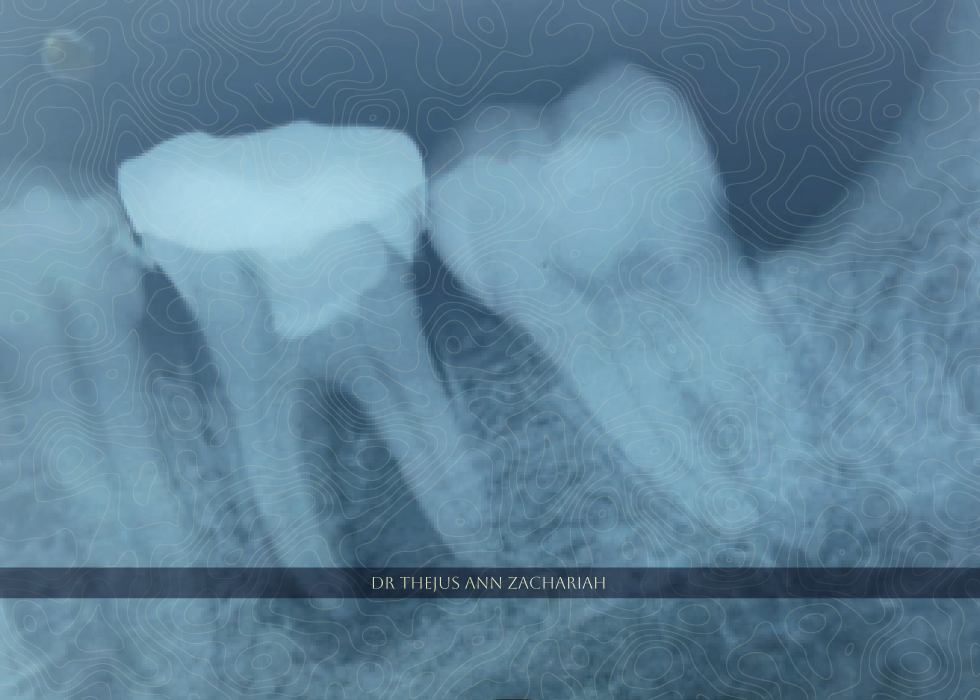

RCT - Through Crown 36

Pre Operative X Ray Failed Previous Vital Pulp Therapy